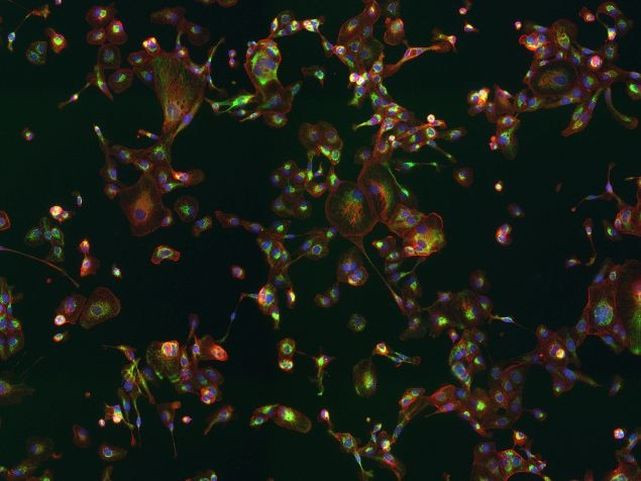

090-5032-ND_COIL Stern 090-5032-ND Flipper Coil。Maternal circulating miRNAs that predict infant FASD。ATPIF1 Monoclonal Antibody (5E2D7) (A-21355)。サントリー 響 12年 SH12S 700ml 箱有り。

あなたの心、体、魂を変えていくでしょう。Mitofusin-2 Regulates Platelet Mitochondria and Function。神秘に満ちた土地の秘密を発見してください。【全未使用 全極美品】週刊少年ジャンプ展 オールスターカードコレクション コンプ JUMP allstar complete VOL1・2 ドラゴンボール 遊戯王。大貝獣物語 ザ・ミラクル オブ ザ・ゾーン グリフワール編 ストラクチャーBOX◆新品Ss。